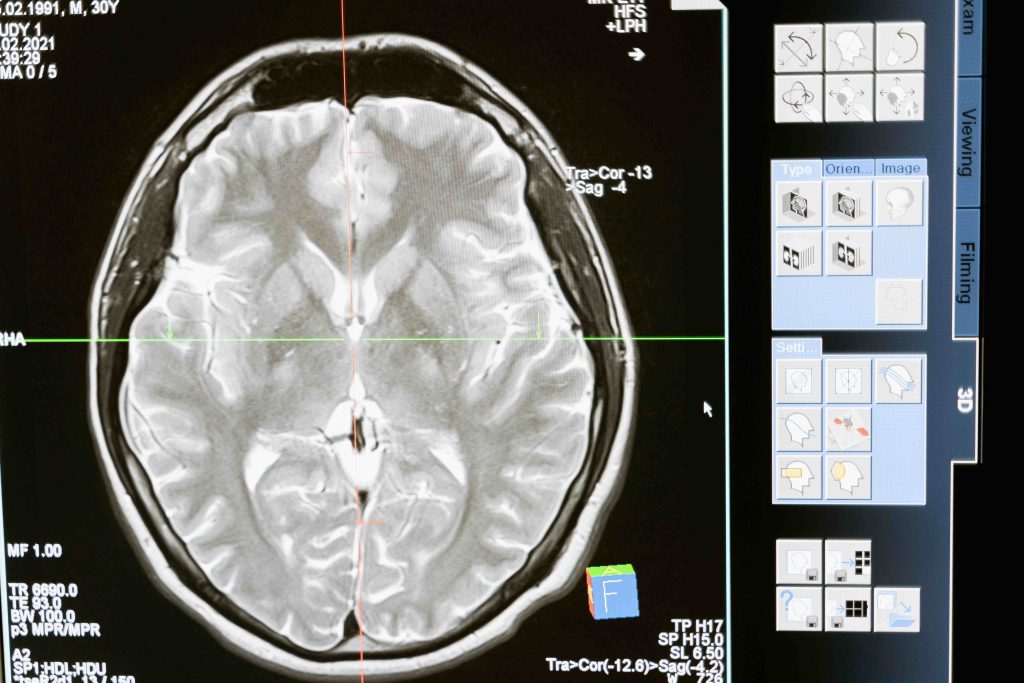

If you or someone you know exhibits any of these symptoms following a head injury, it is essential to seek immediate medical attention. A healthcare professional can conduct a thorough evaluation and provide a diagnosis based on clinical assessments, imaging tests, and other diagnostic tools.